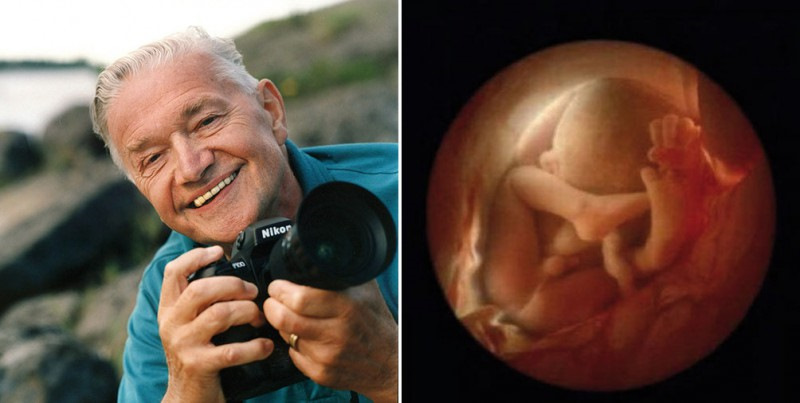

Работы знаменитого фотографа Леннарта Нильссона

Раздел: Фотопанорама